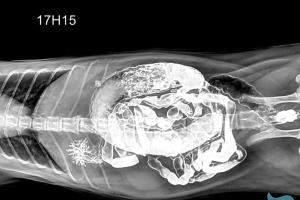

4.3. X-quang toàn thân

Hỗ trợ phát hiện tổn thương phối hợp, gãy nhiều xương hoặc chấn thương nội tạng sau tai nạn.